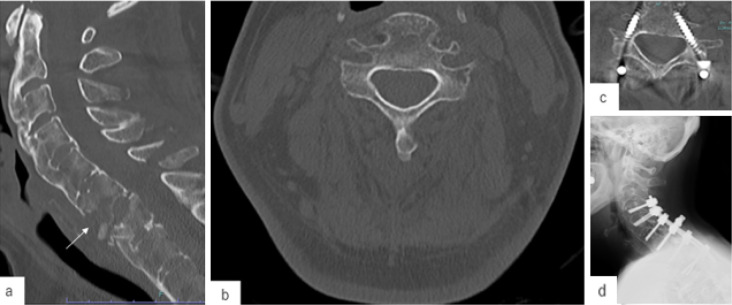

Methods: A retrospective analysis of 36 patients who underwent posterior cervical fusion surgery with CPS placement was conducted using preoperative computed tomography (CT)-based navigation. Cases with CPS insertion at C1 or C2 were excluded. The key morphological parameters-optimal screw trajectory angle, pedicle diameter, and distance from the entry point to the pedicle isthmus (DEP)-were measured on preoperative CT images. CPS placement accuracy was assessed postoperatively using Neo's classification. The receiver operating characteristic (ROC) curve analysis determined the cutoff values for predicting CPS perforation.

Results: Among the 102 CPSs placed from C3 to C7, the overall perforation rate was 25.5%. C3 had the highest perforation rate (45.5%), whereas C7 had the lowest (3.1%). The vertebrae with CPS perforation exhibited a significantly larger optimal screw trajectory angle (45.5° vs. 38.0°, p<0.001), smaller pedicle diameter (4.2 mm vs. 5.2 mm, p<0.001), and longer DEP (13.2 mm vs. 11.9 mm, p=0.002). The ROC analysis identified the following cutoff values: 44.0° for the optimal angle, 4.35 mm for the pedicle diameter, and 12.7 mm for the DEP. These morphological parameters strongly predicted the risk of CPS perforation.